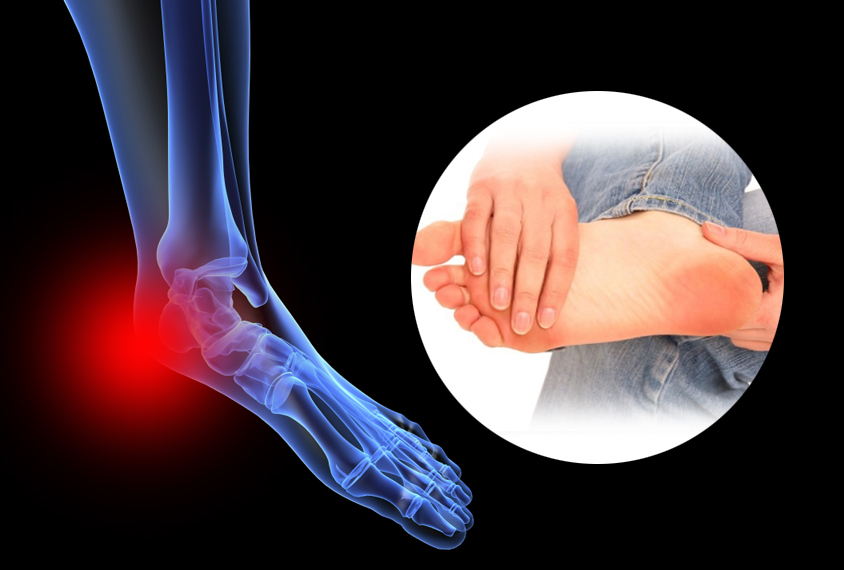

족저 근막염은 발바닥에 위치한 족저근막에 염증이 생기는 질환으로, 발꿈치에 통증을 유발합니다. 주로 하루 중 첫 번째 걸음에서 통증이 심하게 나타나며, 장기간 서 있거나 걷는 것에 어려움을 겪을 수 있습니다. 과도한 운동이나 비만, 잘못된 신발 착용 등으로 발병할 수 있습니다.

족저 근막염의 가장 흔한 증상은 발꿈치 통증입니다. 첫 걸음을 디딜 때 통증이 가장 심하며, 일상적인 활동 중에도 통증이 발생할 수 있습니다. 통증은 발꿈치 안쪽에서 느껴지는 경우가 많습니다.